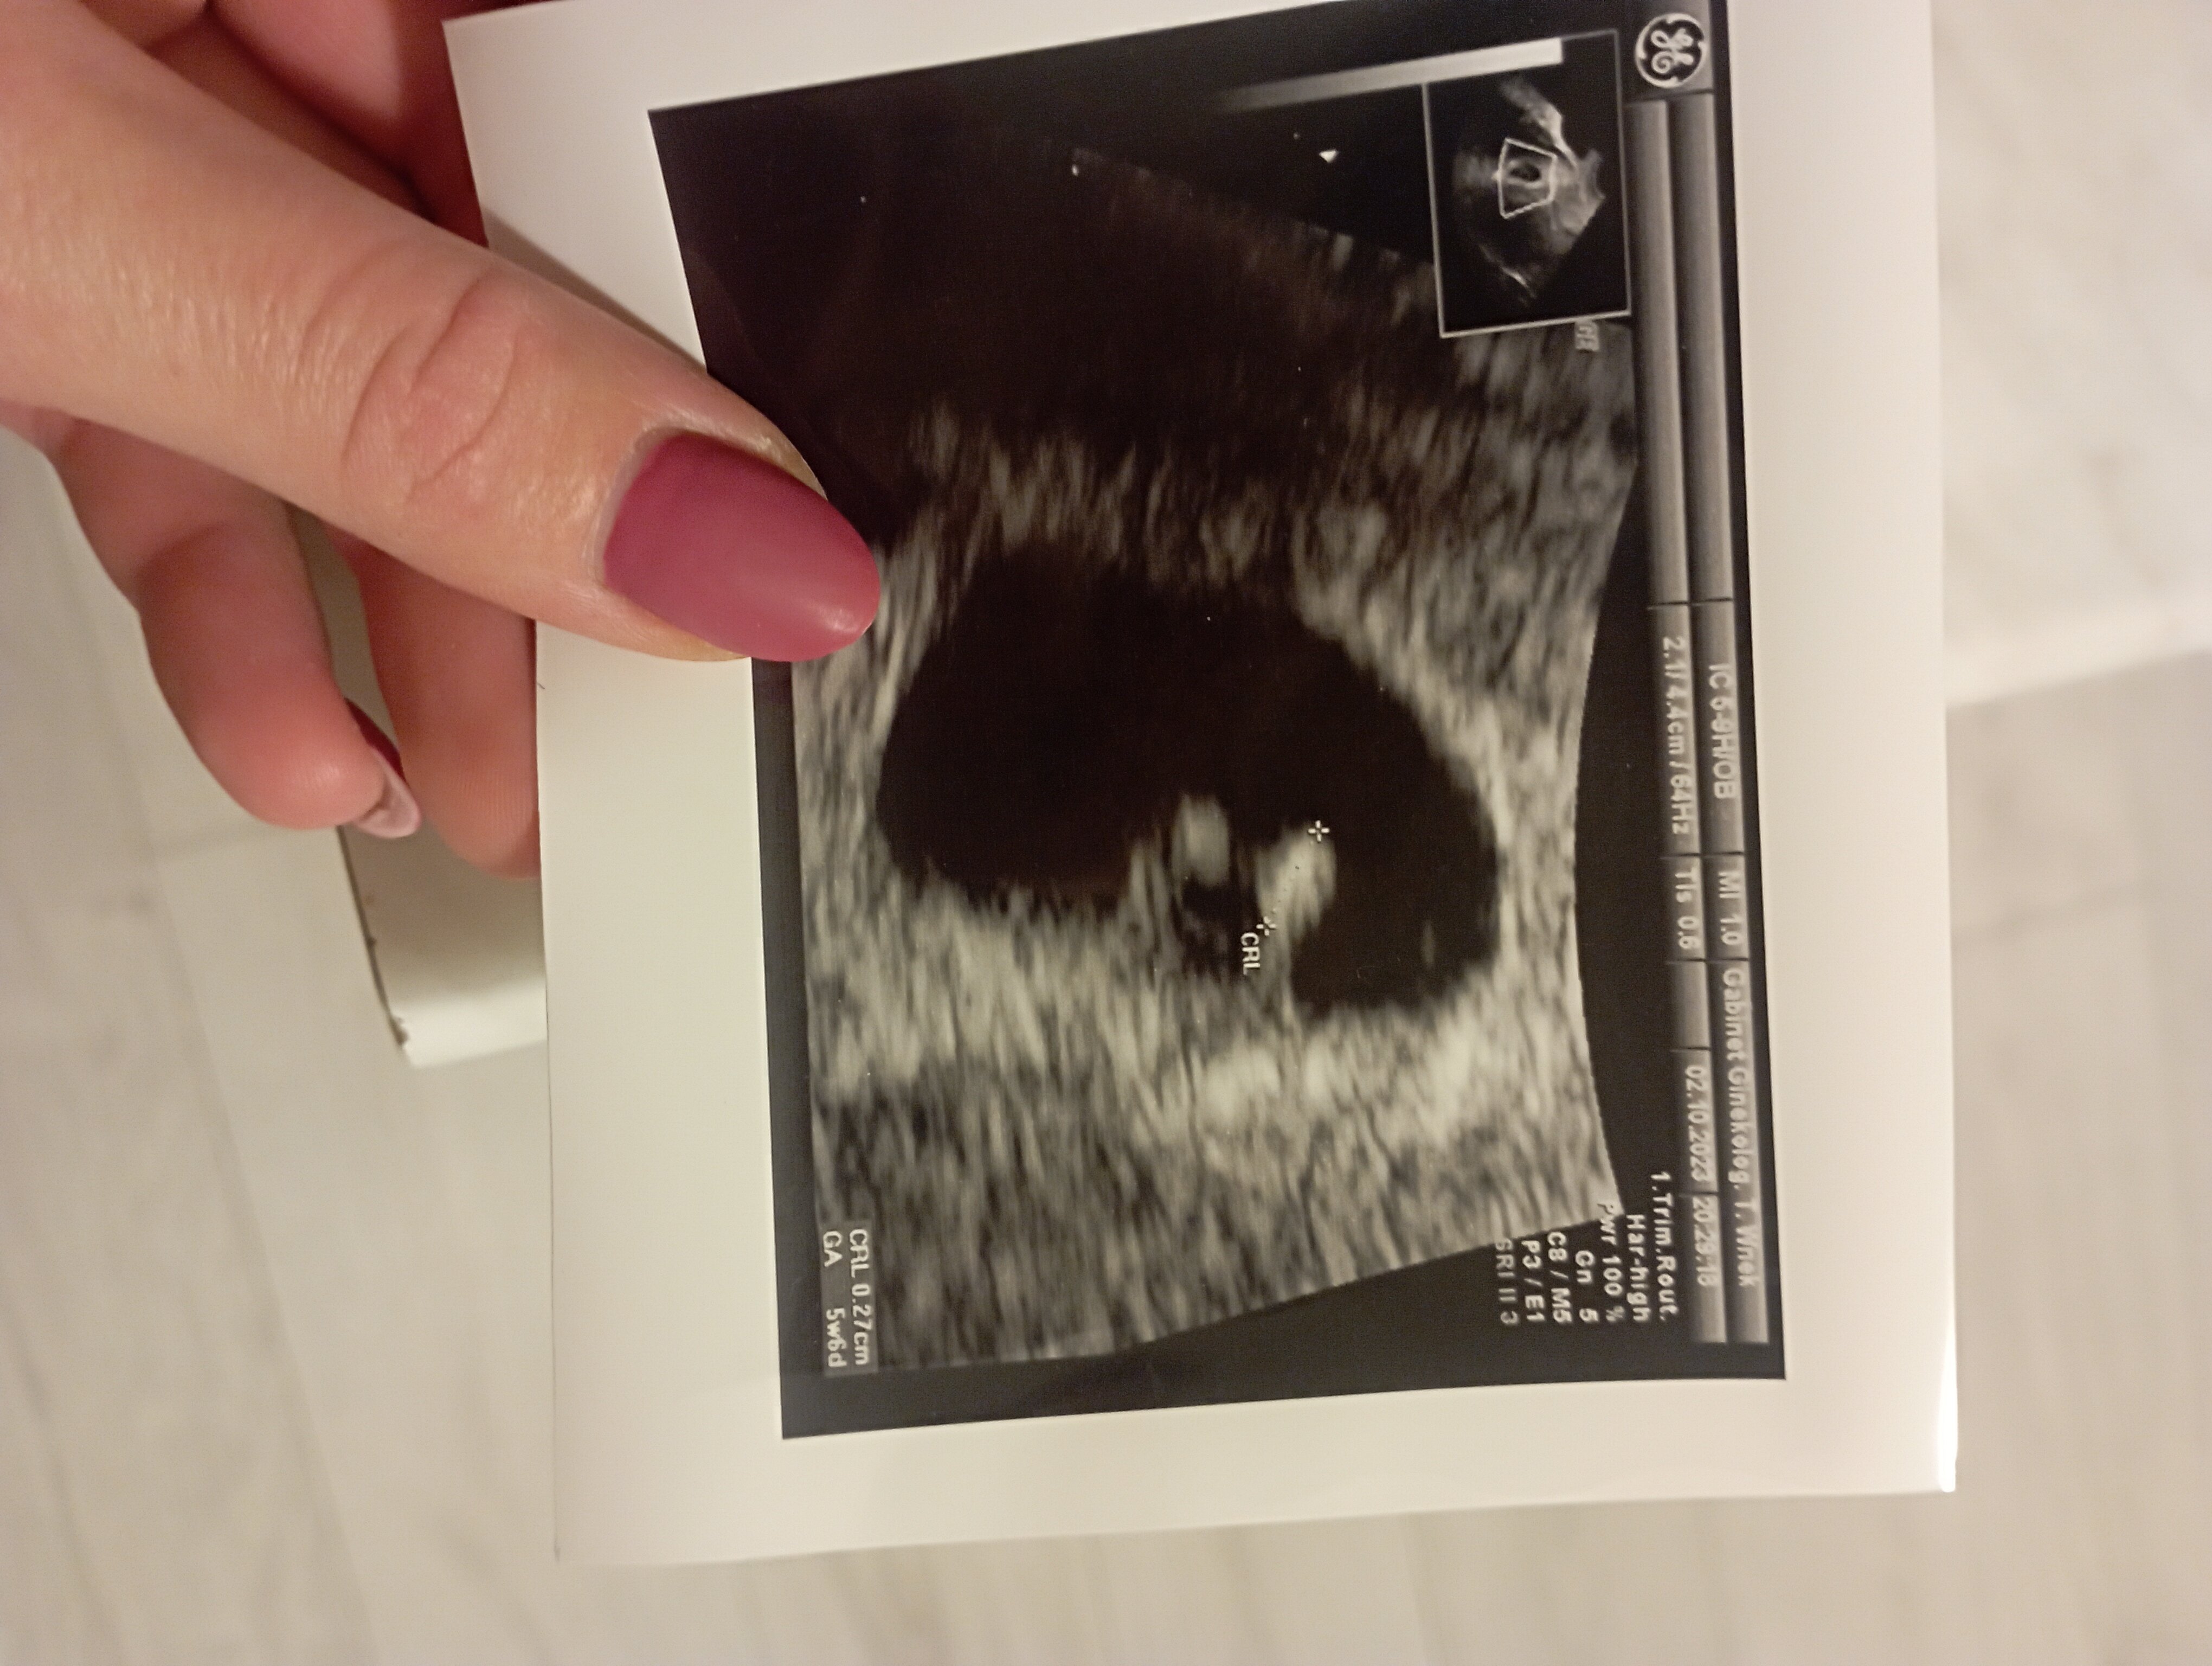

5+6. Jest zarodek :) za trzy tygodnie wizyta :)

Załączniki

• IMG_20231002_201002.jpg

IMG_20231002_201002.jpg

1,2 MB · Wyświetleń: 127